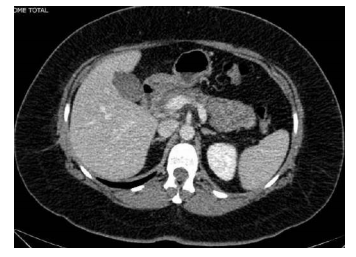

Um paciente de 51 anos de idade, sem comorbidades, iniciou, há três dias, quadro de fortes dores em hipocôndrio direito e epigástrio, com vômitos após refeição copiosa. Fez uso de analgésicos comuns, mas, como houve piora da dor, procurou o atendimento do seu médico particular. O médico solicitou exame de imagem e exame laboratorial para investigação. Nos exames laboratoriais, Hb 13 g/dL, leucócitos 14.000/mm3 , TGO e TGP dentro da normalidade, bilirrubina total 3,2 mg/dL, bilirrubina direta 2,8 mg/dL, amilase 650 U/L, ureia 28 mg/dl, creatinina 1,2 mg/dL, fosfatase alcalina 110 mg/dL, gama GT 320 mg/dL e PCR 5 mg/dL. Realizou uma ultrassonografia, que revelou colelitíase, e a tomografia cuja imagem é mostrada a seguir. Após avaliar os exames, o médico encaminhou o paciente ao pronto-socorro.